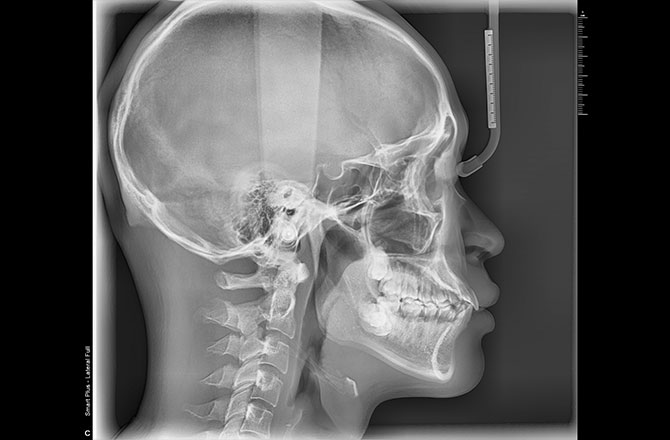

3DCT撮影とセファロ分析で

より精密な治療を

矯正治療では、見た目の歯並びだけではなく、骨格や顎の位置関係を正確に把握することが欠かせません。

当院では3DCTとセファロ分析を併用し、歯の傾きや顎の位置関係、成長の傾向などを詳細に診断します。

これにより、治療後の変化を予測しやすくなり、より精度の高い治療計画を立てることが可能です。